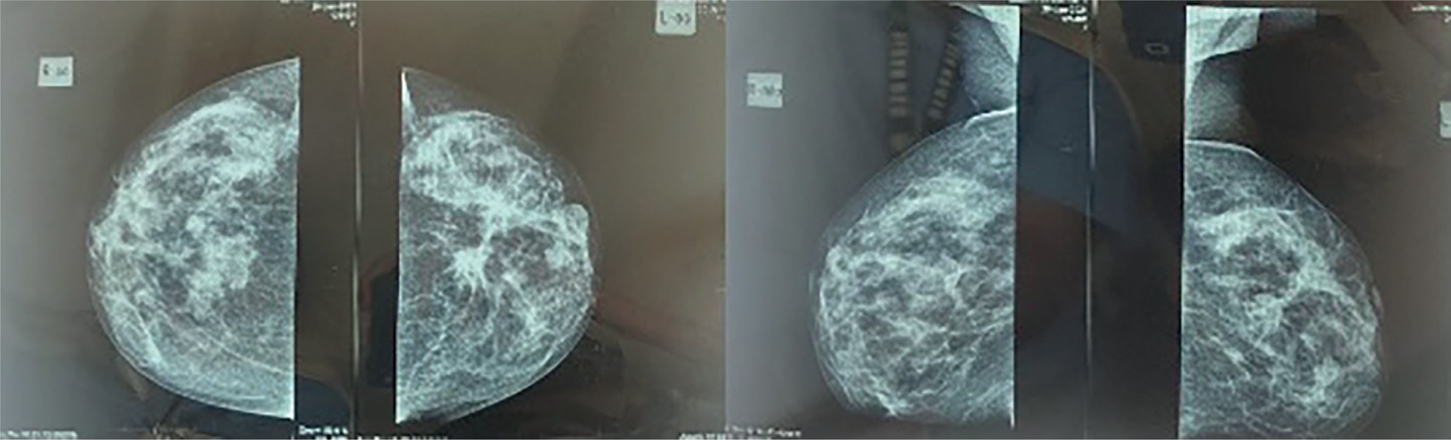

Post-Treatment MFBI

Post-operative MFBI or MRI is not routinely implemented to evaluate outcomes of surgical procedures due to strong enhancements of inflammatory tissues post-operatively in the acute phase. Consequently, immediate breast MRI is not recommended until 12 to 18 months after the procedures. The current guidelines do not recommend MFBI in treated breast cancer, and MRI is mostly indicated if recurrence of metastatic foci is suspected. However, breast MRI is eventually superior to detecting developing neo-density or other suspicious structures (7, 52, 53). In post-surgery settings, the result of MRI imaging is classified into enhancing mass, non-mass-like enhancement (NMLE), or suspected foci––with the characteristic of each focus fully described, for example, size, shape, margin (smooth, irregular, or even spiculated), and internal enhancement pattern (Figure 2). NMLE findings are elaborated according to their distributions along the breast tissue (focal, regional, segmental, scattered, or involving multiple regions), internal enhancement pattern, and symmetry. Foci that are too small to be optimally described (usually ≤5 mm in diameter) are defined as “indescribable” lesions (5355).

Fig 2

Figure 2. Malignant findings on breast MRI. Image provided by Division of Oncology, Department of Surgery, Faculty of Medicine, Universitas Sumatera Utara)